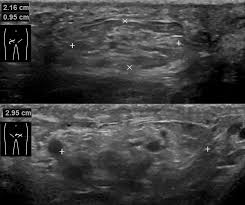

- 신장 결석

- 신장 낭종